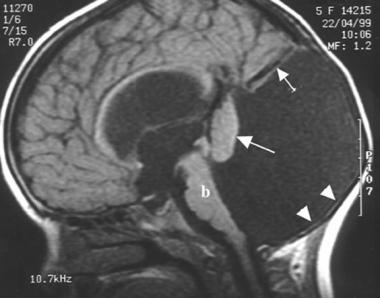

Dandy-Walkerov syndróm (anglicky Dandy-Walker syndrome, Dandy-Walker malformation, DWS) je zriedkavé vrodené neurologické ochorenie mozgu. Príčinou tohto ochorenia je tzv. Dandy-Walkerova malformácia, ktorá spočíva v aplázii (nevyvininutí) vermis, t.j. špecifickej časti mozočku, a vo vzniku veľkej cysty v zadnej jame lebečnej, ktorá je široko otvorená do IV. komory.

Následkom tejto vrodenej zmeny tkaniva mozočku je membranózna atrézia (nepriechodnosť) otvorov IV. komory mozgovej, čím dochádza k patologickému hromadeniu mozgomiešneho moku v mozgových komorách.

• cysta v zadnej jame lebečnej, ktorá komunikuje so IV. mozgovou komorou

• veľmi priestranná zadná jama lebečná